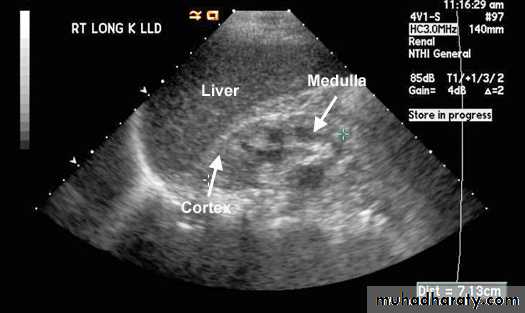

Normal Kidney; Normal kidney measures between 10.5 to 12.5 cms. Cortex is about 2.5 cms and has the same kind of echoes as liver. Medulla is hypoechoic and appears dark.

Chronic Renal Failure; Kidneys are smaller than normal. Surface may be irregular. Cortex is thinned and is hyperechoic than liver due to scar tissue. Medulla is hypoechoic and appears dark.